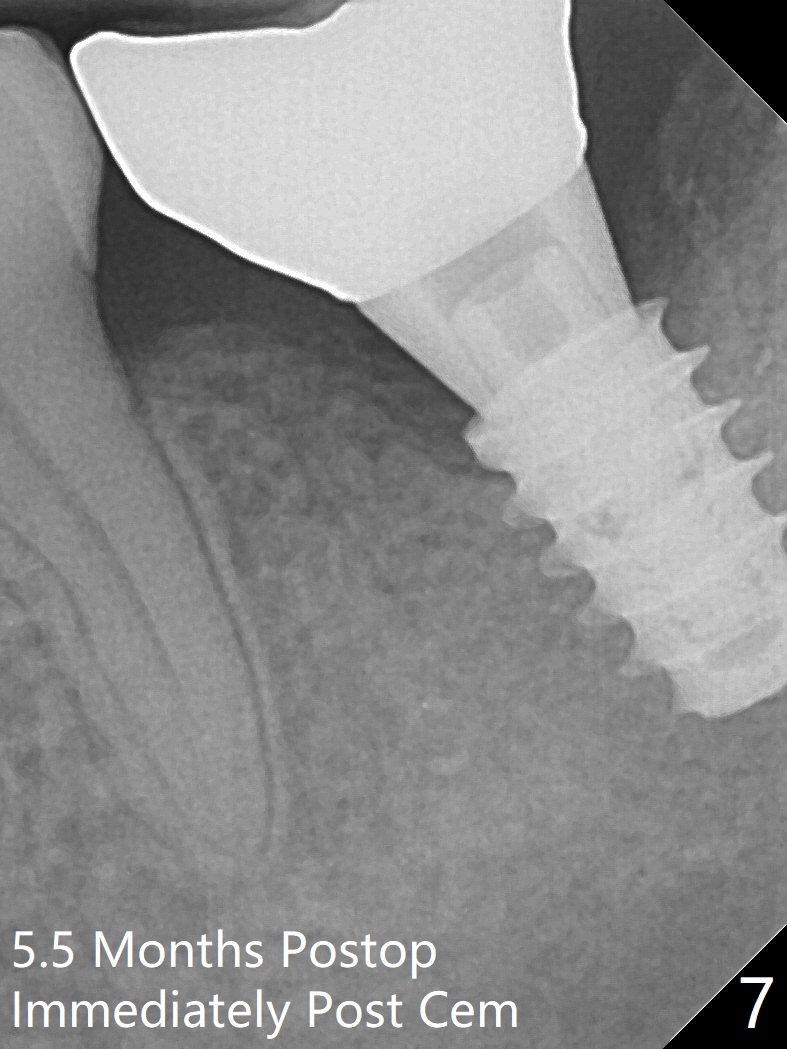

Six months post socket preservation at #18 (with moderate atrophy, Fig.1), a simplified surgical guide (Fig.2 with metal sleeve of 5 mm height and 2.93 mm diameter) determines initial osteotomy with 3.3 mm Magic Drill (MD), followed by 4.8 mm MD for 9 mm (gingival level) free hand. Since a 5x7 mm IBS implant is placed incompletely and in low stability (Fig.3 (in the graft bone)), a 4.3 mm MD is used for ~1 mm deeper. The implant is reseated to more satisfactory level (Fig.4: ~ 1 mm from the upper border of the Inferior Alveolar Canal (red dashed line)). The fearful patient is extremely pleased with quickness of the procedure as compared to that at #30 free hand. The wound heals normally 2 weeks postop. When she finishes the follow up appointment, she voluntarily talks to another patient who is hesitant about implant treatment. Impression is taken 5 months postop (Fig.5,6). There is no gap between the crown and abutment using abutcoping technique (Fig.7,8). The crown at #18 looks low probably related to long termed edentulism (Fig.9). The access hole is lingual (Fig.9), because the implant was placed lingual (Fig.10) due to use of a partial guide (Fig.11).